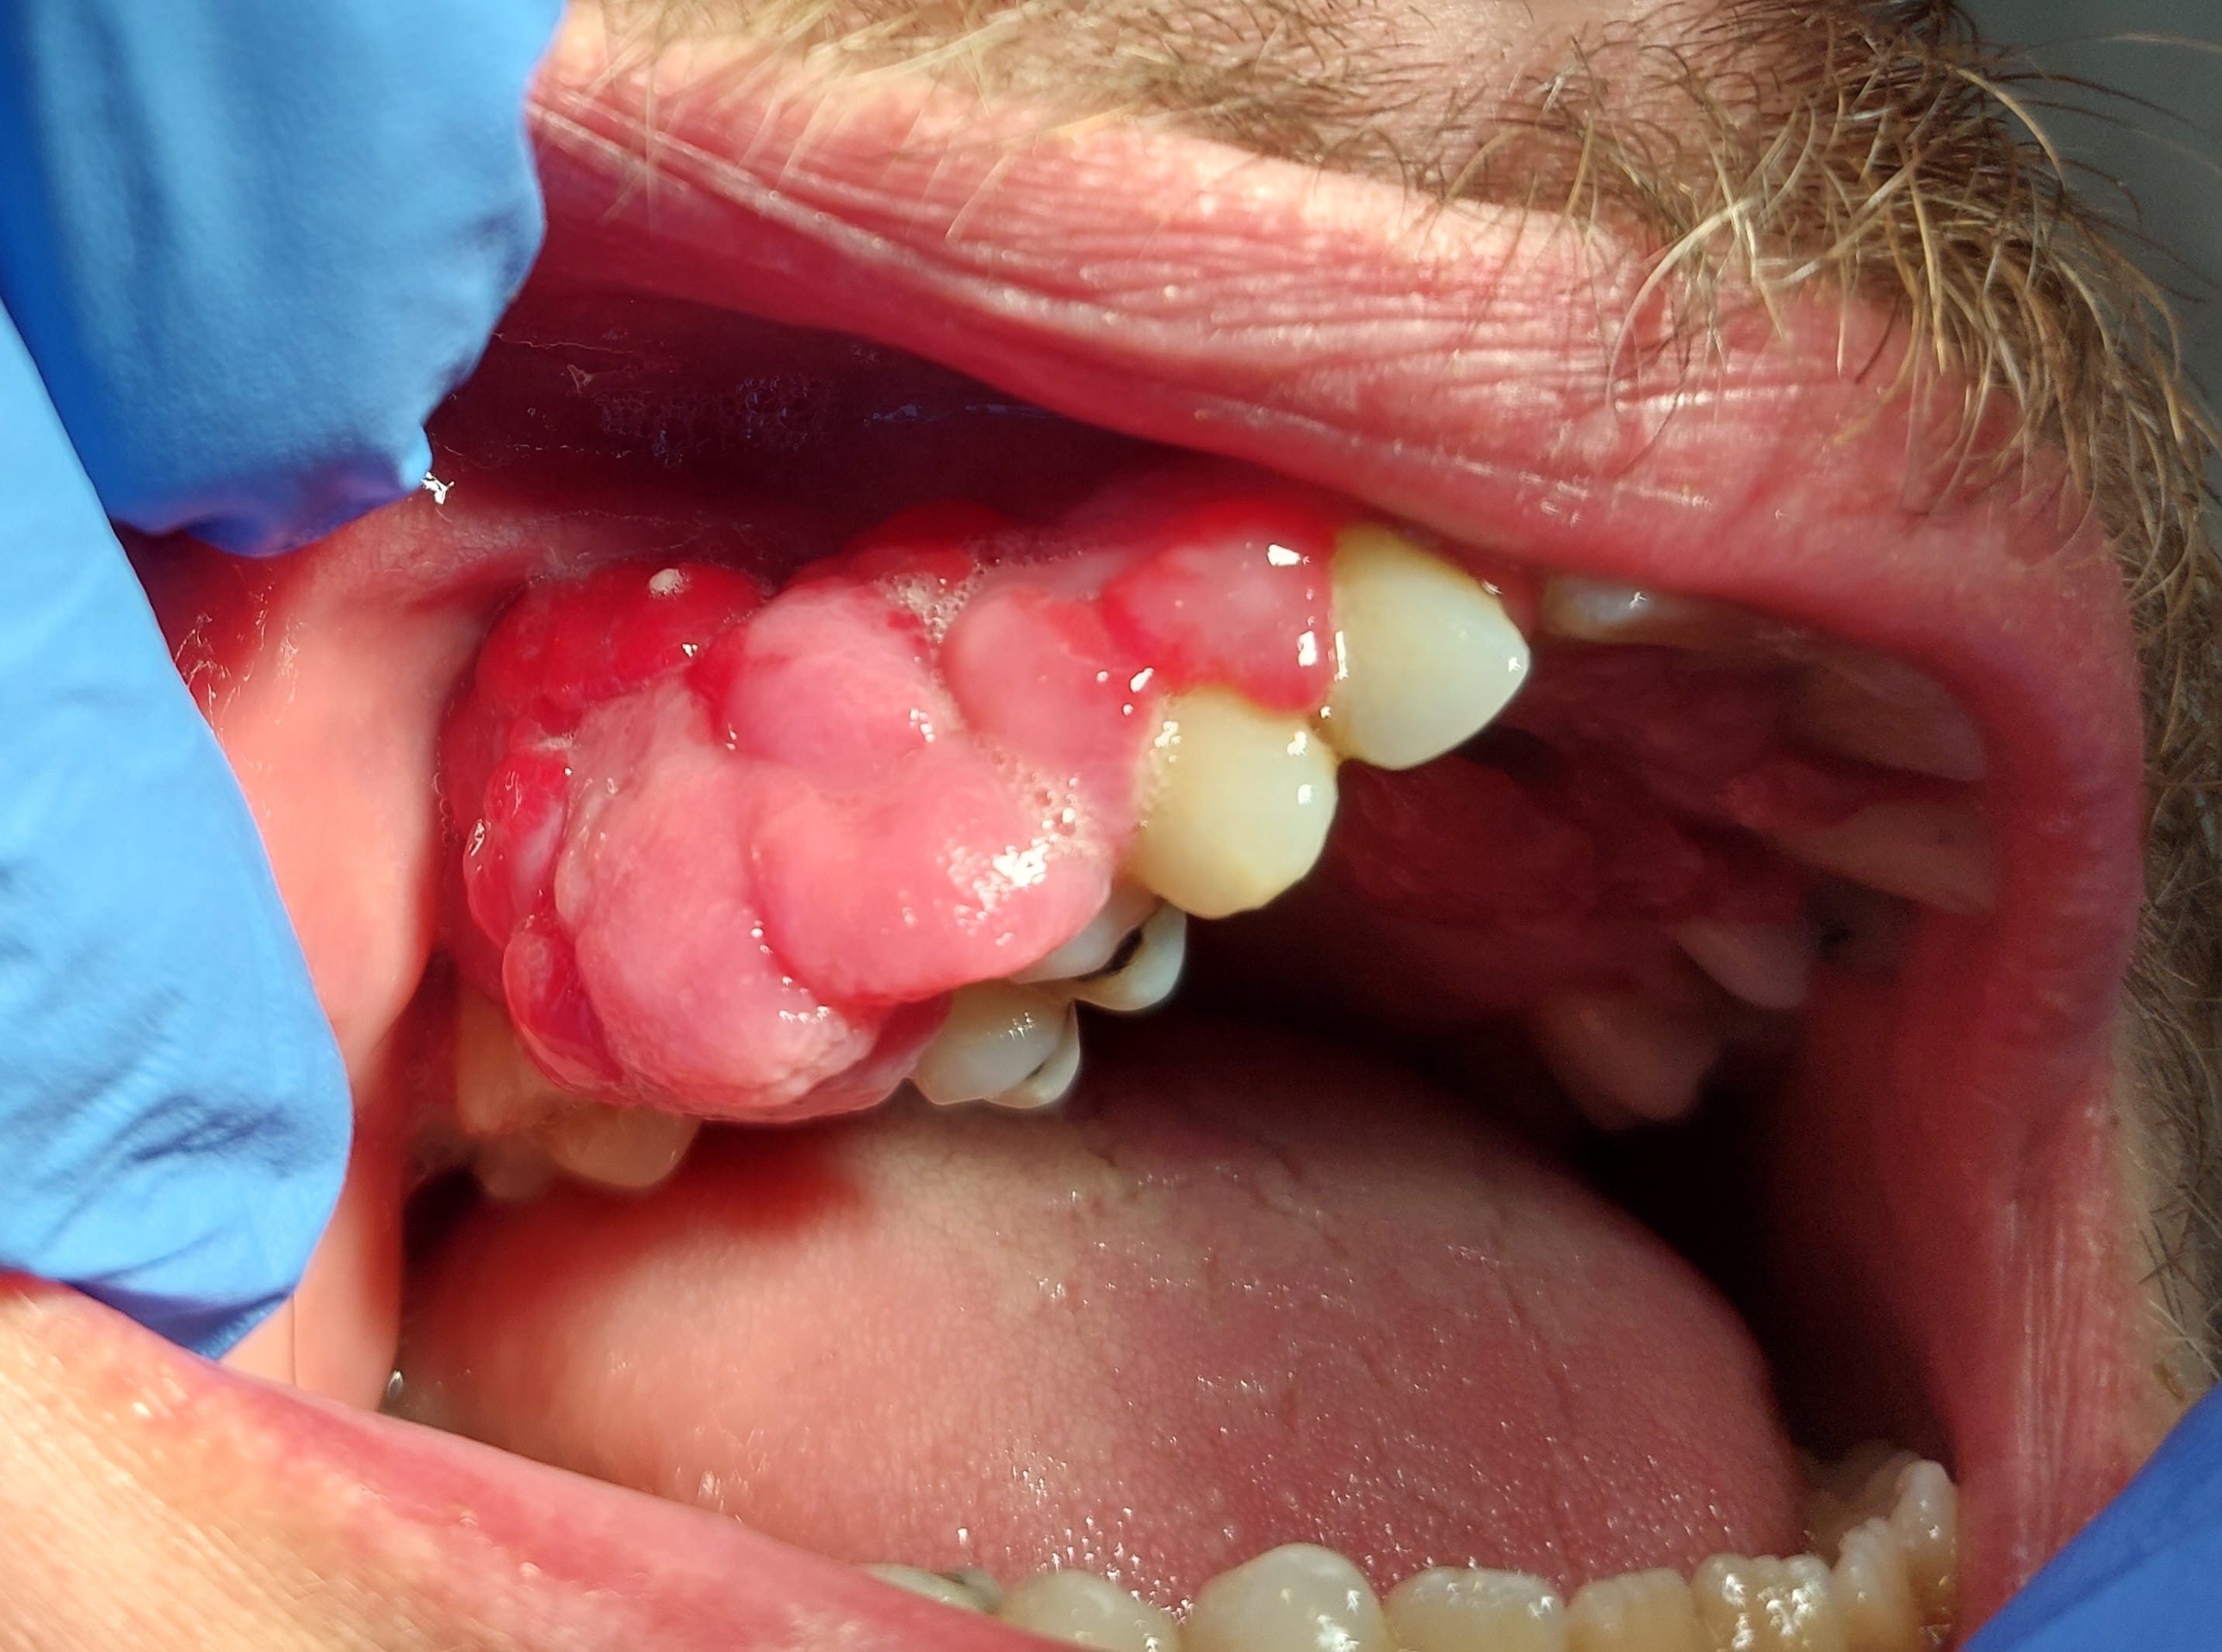

Patient de 31 ans, hépatite B depuis 1995 traitée par baraclude, à priori sans soucis mais pas de prise de sang depuis 6 mois. Également léger retard mental du à un syndrome lié à l'X.

Consulte pour hyperplasie gingivale apparue progressivement en 5 mois (RAS avant d'après lui), totalement indolores, pas de saignement sauf en insistant aux collets en gingivite.

Les 2 principales zones hyperplasiques dans le vestibule secteur 10 et palatin secteur 20 sont bien pédiculées et mobiles.

Voilà les photos.